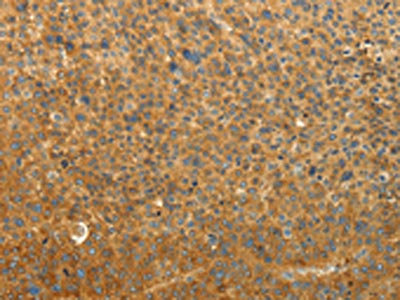

The image on the left is immunohistochemistry of paraffin-embedded Human thyroid cancer tissue using CSB-PA140113(RAB35 Antibody) at dilution 1/50, on the right is treated with synthetic peptide. (Original magnification: ×200)

The image on the left is immunohistochemistry of paraffin-embedded Human liver cancer tissue using CSB-PA140113(RAB35 Antibody) at dilution 1/50, on the right is treated with synthetic peptide. (Original magnification: ×200)